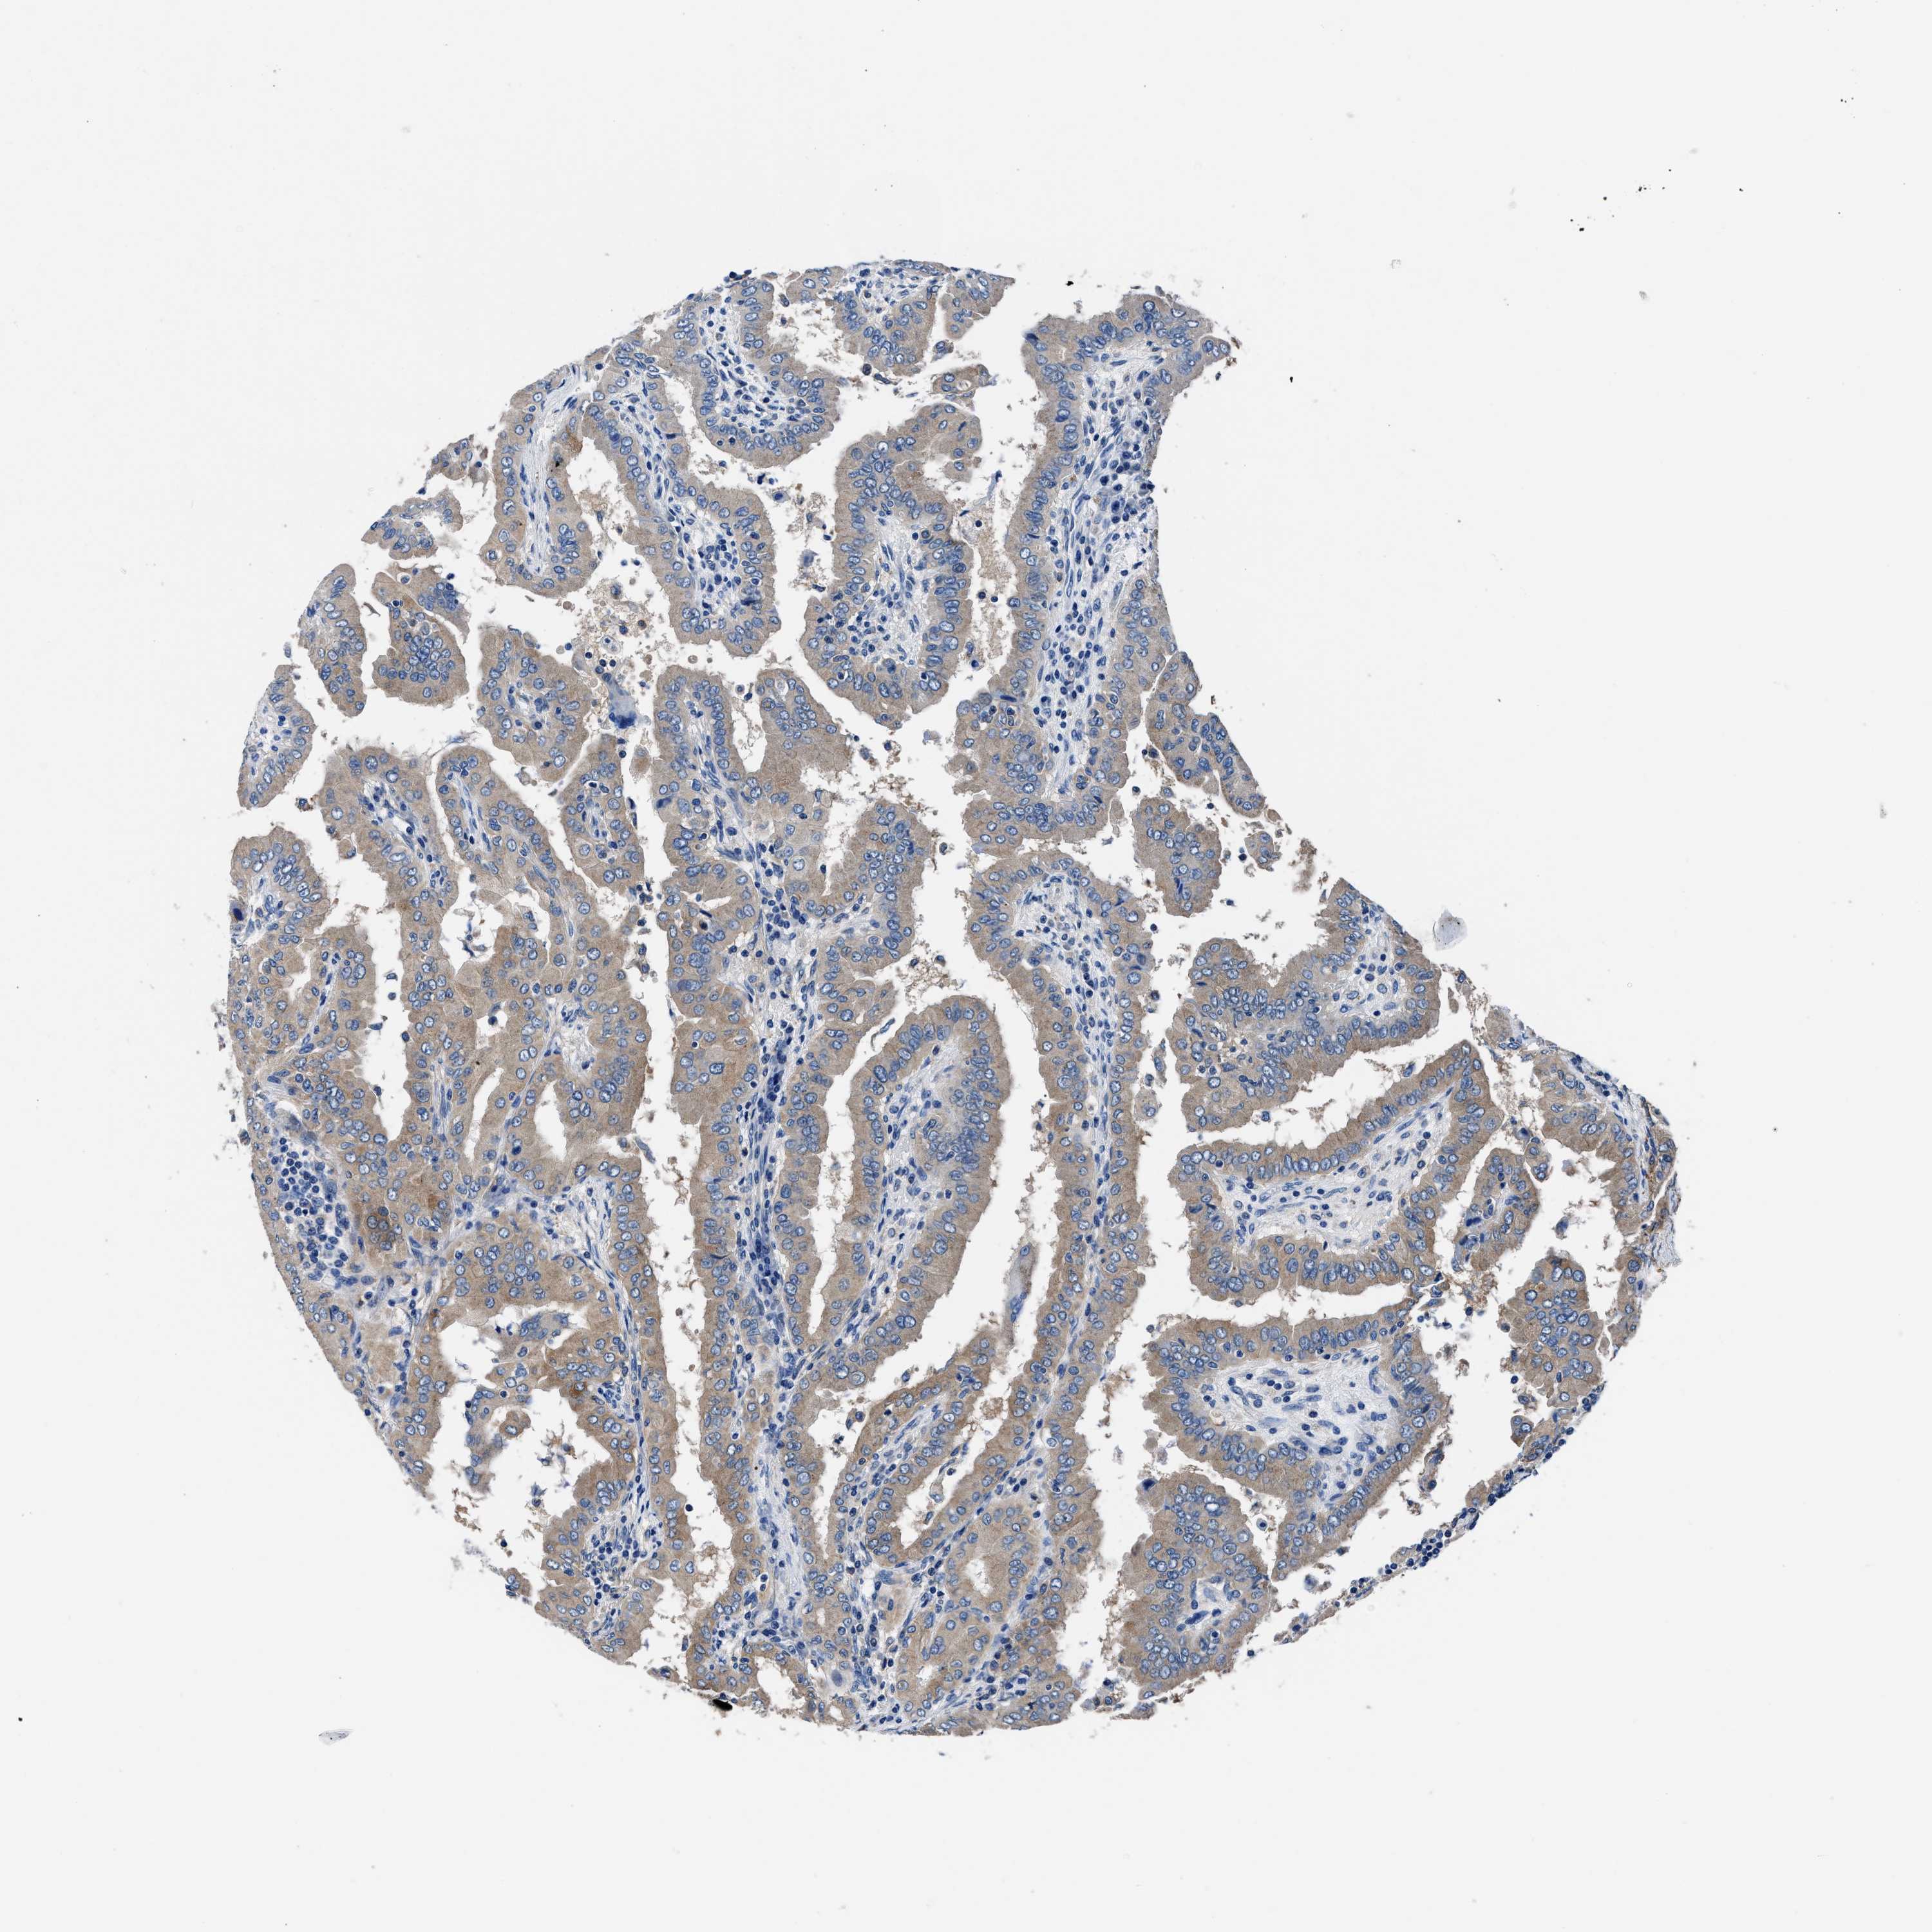

THYROID CANCER - Protein expressioni

A mouse-over function shows sample information and annotation data. Click on an image to view it in a full screen mode. Samples can be filtered based on level of antibody staining by selecting one or several of the following categories: high, medium, low and not detected. The assay and annotation is described here.

Note that samples used for immunohistochemistry by the Human Protein Atlas do not correspond to samples in the TCGA dataset.

Antibody stainingi

Antibody staining in the annotated cell types in the current human tissue is reported as not detected, low, medium, or high, based on conventional immunohistochemistry profiling in selected tissues. This score is based on the combination of the staining intensity and fraction of stained cells.

Each image is clickable and will lead to virtual microscopy that enables deeper exploration of all samples and also displays staining intensity scores, fraction scores and subcellular localization as well as patient and tissue information for each sample.

Antibody HPA015634

Antibody HPA021506

Staining

High

Medium

Low

Not detected

Intensity

Strong

Moderate

Weak

Negative

Quantity

>75%

75%-25%

<25%

None

Location

Nuclear

Cytoplasmic/membranous

Cytoplasmic/membranous,nuclear

Papillary adenocarcinoma, NOS

Follicular adenoma carcinoma, NOS